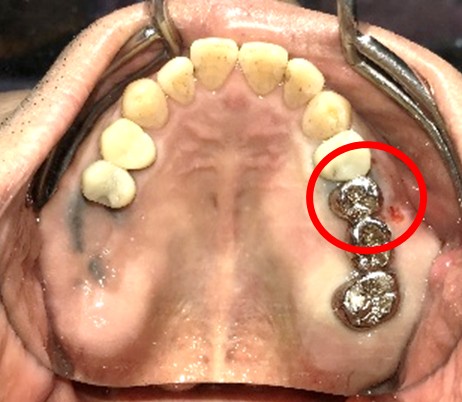

女性Mさん 40代(インプラント)

主訴

下、左右歯がないところに歯を入れたい。

治療内容

右下に2本、左下に1本インプラントを入れました。

所感

下顎左右奥の歯がないところに、インプラント治療を希望されて来院されました。X-Guideを使用し埋入しました。治療後「左右の奥歯でしっかり噛めてうれしいです。」と、とても喜んでくださいました。

インプラント3本:¥363,000×3本=¥1,089,000(税込)

Before

After